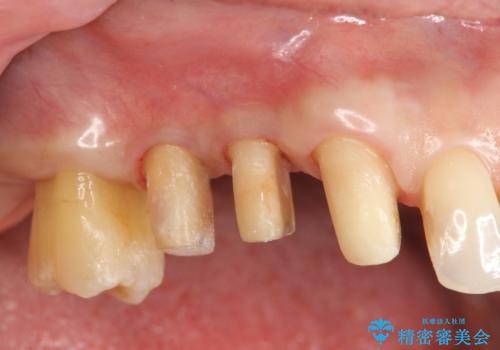

咬合関係の改善、前歯の角度、がたつきを改善するため、マイクロインプラントを用いて上顎の奥歯を後方へ移動させていきます。